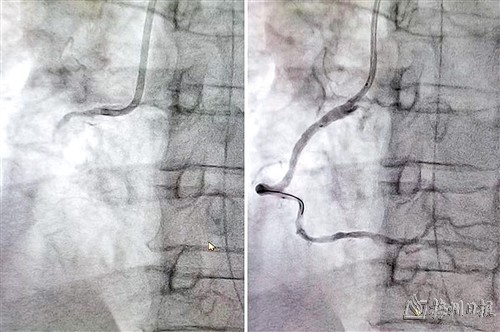

右冠状动脉闭塞,植入支架后再通。

梅州市人民医院心脏重症监护科ECMO团队在30分钟内快速建立VA-ECMO管路,在VA-ECMO支持下成功完成冠脉造影及经皮冠状动脉介入治疗(PCI术),经右冠状动脉球囊扩张后,为患者植入支架,疏通闭塞心脏血管,患者恢复窦性心律。